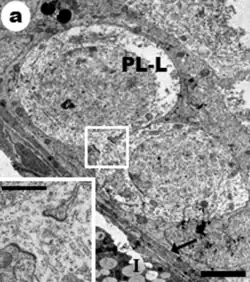

Ultraestructura

Las espermatogonias B, van a permanecer unidas por puentes citoplasmáticos para sincronizarse, de modo que cuando llega la señal todas van a dividirse a la vez. Esta sincronización puede ocurrir sin necesidad de estos puentes, sin embargo, como se encuentran en una zona con mucho empaquetamiento y con muchas células, existen estos puentes para evitar que la señal se propague a otras células.

Compartimento basal

El compartimento basal de los túbulos seminíferos es el área definida entre la lámina basal del túbulo y las uniones estrechas o (thigth junctions en inglés), de las células de Sertoli.

Las espermatogonias Ad contienen una zona de rarefacción que no se tiñe, dentro de un núcleo que se tiñe de oscuro.

Los núcleos de espermatogonias Ap se tiñen de forma ligera y uniforme.